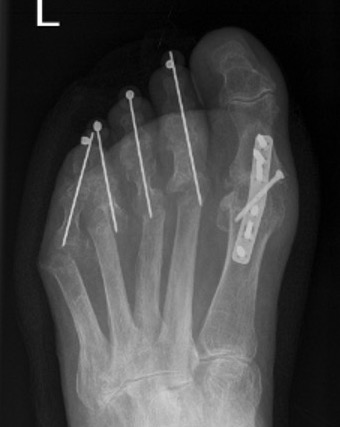

Operative Options

Synovectomy / Weil's osteotomy / Fowler's procedure (excision arthroplasty)

- Weil osteotomy in 72 RA feet

- 88% good or excellent results

- recurrent / persistent subluxation in 14%

Horita et al Foot Ankle Int 2018

- 16 resection arthroplasty v 18 Weil osteotomy in RA

- resection: outcome score 84, recurrence 3 feet

- osteotomy: outcome score 90, recurrence 1 foot

Fowler's Procedure - metatarsal head excision

Dorsal transverse skin excision just proximal to toe webs

- can be performed via transverse plantar ellipse

- with severe dislocation may be easier to approach through plantar aspect

Extensor tenotomy

Cascading excision of II - V metatarsal heads

- dorsal distal to plantar proximal

- contoured on plantar surface to give rounded surface